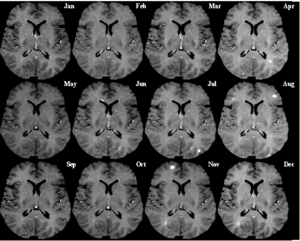

وتختلف أعراض التصلب المتعدد وفقًا للمناطق المصابة من الدماغ والحبل الشوكي. وبمرور الزمن يتزايد تكوّن اللويحات في الغمد النخاعي للمريض، مما يتسبب في ظهور أعراض جديدة. ويشخِّص الأطباء التصلب المتعدد بصفة رئيسية بناء على الأعراض، وهناك تقنية تسمى التصوير بالرنين المغنطيسي النووي يمكن أن يساعد في التشخيص، وذلك بإعطاء صور اللويحات داخل الدماغ.

لمرض التصلب المتكرر لا يقتل الإنسان بصورة عامة . أكثر المرضى المصابون بهذا المرض يعيشون بنفس العمر تقريباً الذي يعيشه الإنسان الغير مصاب بهذا المرض . الفحص السريري هو الأساس وفي العصر الحاضر أصبح أهم فحص يثبت التشخيص بالإضافة للفحص السريري هو التصوير بالأشعة المغناطيسية ((MRI إن الأشعة المغناطيسية تعطي صورة دقيقة للمخ والحبل الشوكي وتبين الأماكن التي أصيبت بالالتهابات بحيث يراها الطبيب كنقط بيضاء على الأشعة . وفي أحيان معينة قد يحتاج المريض إلى عمل فحص للعينين أو أخذ وخزة يعني إبرة من السائل السحائي من ظهر المريض لفحص بعض المواد.